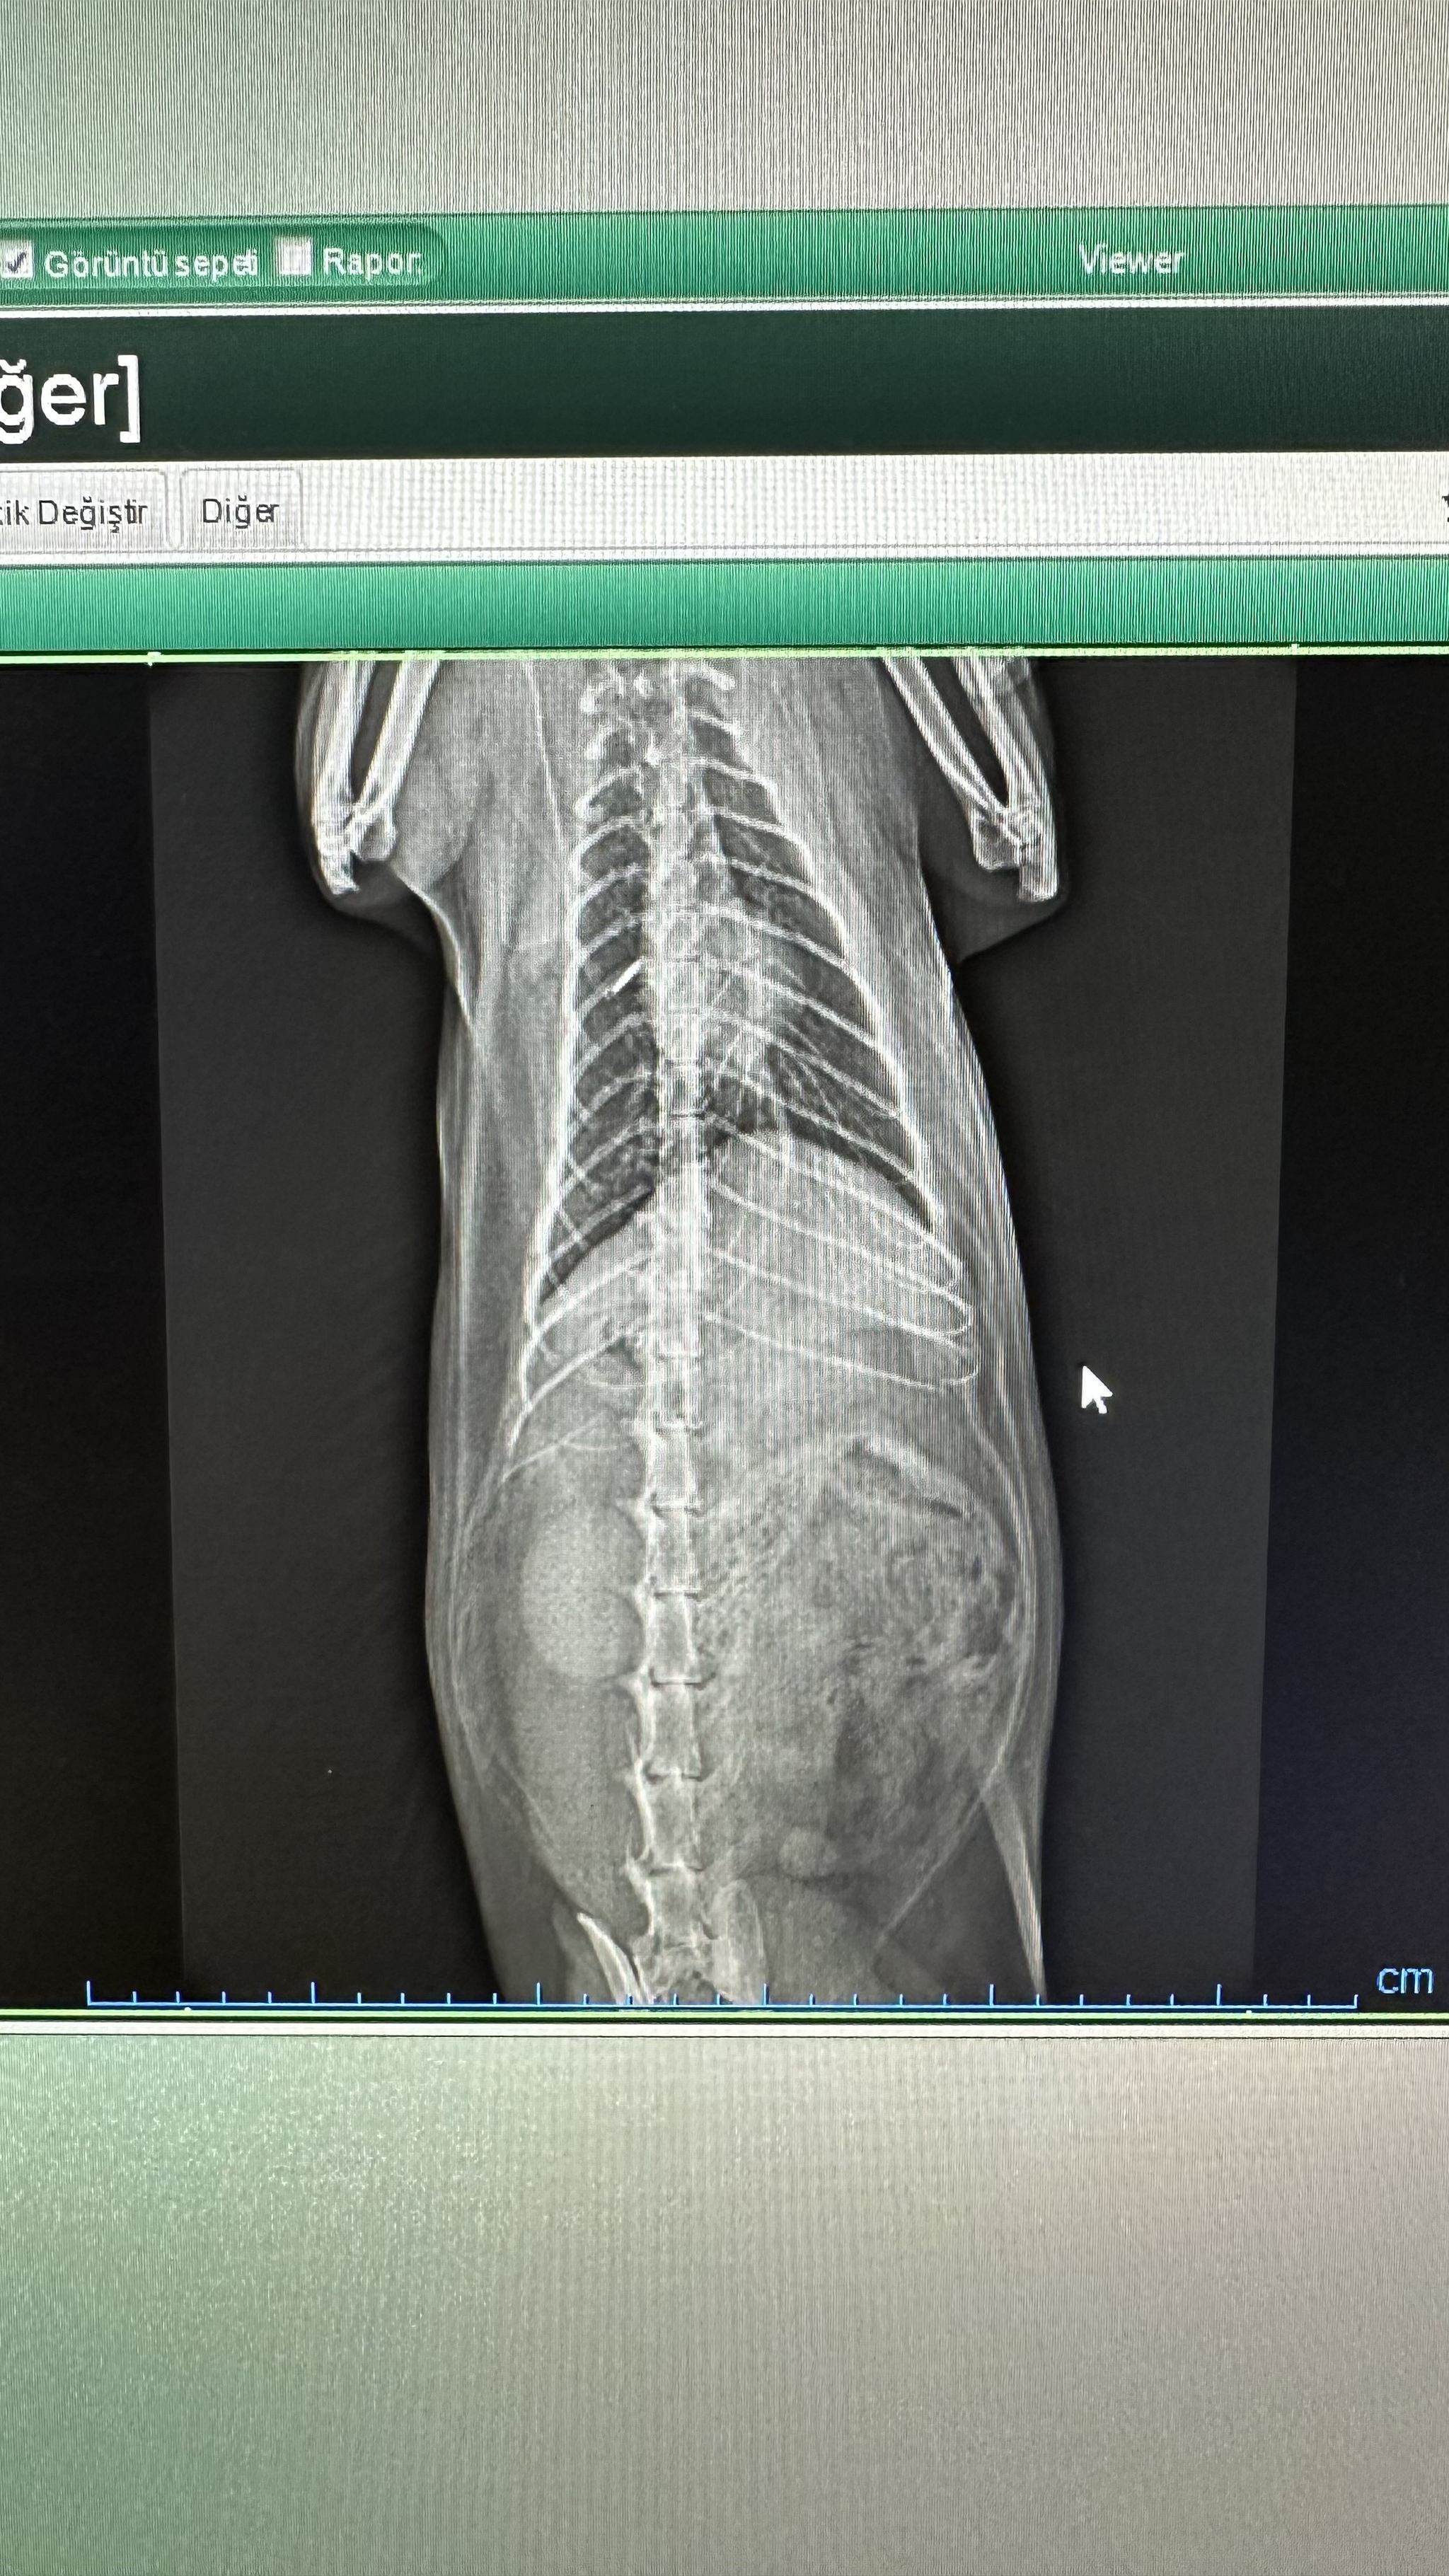

Коту три года. В 2022 увидели, что кот кашляет, как будто комок шерсти срыгивает, но не может. Такое явление повторялось редко, может, раз в несколько месяцев. Но сейчас интервал между такими приступами уменьшился. Когда первый раз ходили к ветеринару с этой проблемой, сказал, что ничего страшного. (территориально находимся в Турции, обращаемся к местным докторам). Сегодня отнесли кота к другому ветеринару, она сделала только рентген, сказала, что увеличено сердце, левая почка и грибок в лёгких. Выписала: Semitra (1мл/1кг веса), экстракт калины и Royal Canin Urinary. Пить семь дней, потом снова на рентген.